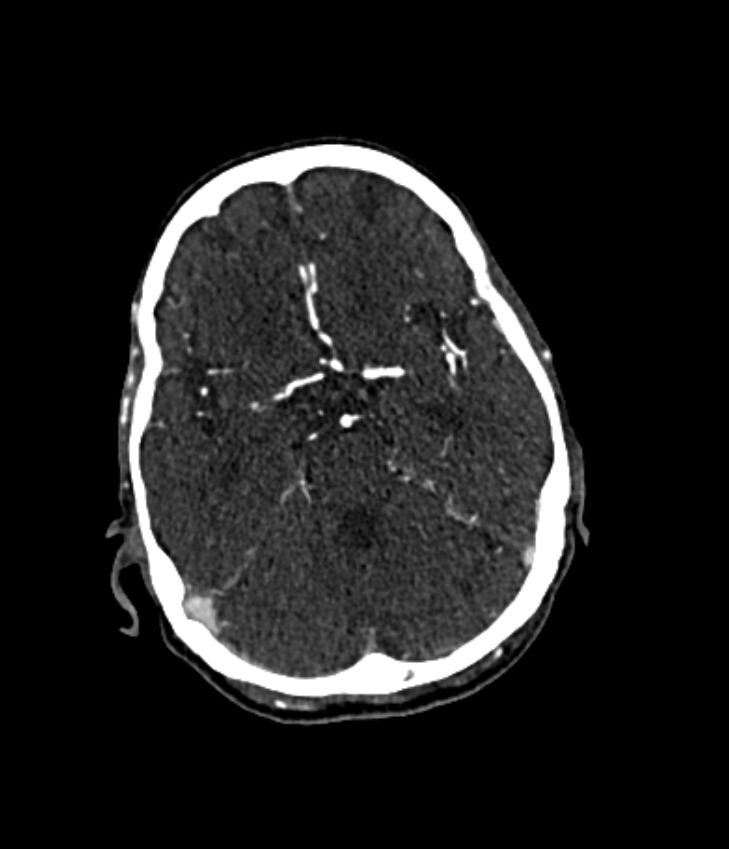

During the diagnosis of ischemic strokes, the Circle of Willis and its surrounding vessels are the arteries of interest. Their visualization in case of an acute stroke is often enabled by Computed Tomography Angiography (CTA). Still, the identification and analysis of the cerebral arteries remain time consuming in such scans due to a large number of peripheral vessels which may disturb the visual impression. In previous work we proposed VirtualDSA++, an algorithm designed to segment and label the cerebrovascular tree on CTA scans. Especially with stroke patients, labeling is a delicate procedure, as in the worst case whole hemispheres may not be present due to impeded perfusion. Hence, we extended the labeling mechanism for the cerebral arteries to identify occluded vessels. In the work at hand, we place the algorithm in a clinical context by evaluating the labeling and occlusion detection on stroke patients, where we have achieved labeling sensitivities comparable to other works between 92\,\% and 95\,\%. To the best of our knowledge, ours is the first work to address labeling and occlusion detection at once, whereby a sensitivity of 67\,\% and a specificity of 81\,\% were obtained for the latter. VirtualDSA++ also automatically segments and models the intracranial system, which we further used in a deep learning driven follow up work. We present the generic concept of iterative systematic search for pathways on all nodes of said model, which enables new interactive features. Exemplary, we derive in detail, firstly, the interactive planning of vascular interventions like the mechanical thrombectomy and secondly, the interactive suppression of vessel structures that are not of interest in diagnosing strokes (like veins). We discuss both features as well as further possibilities emerging from the proposed concept.